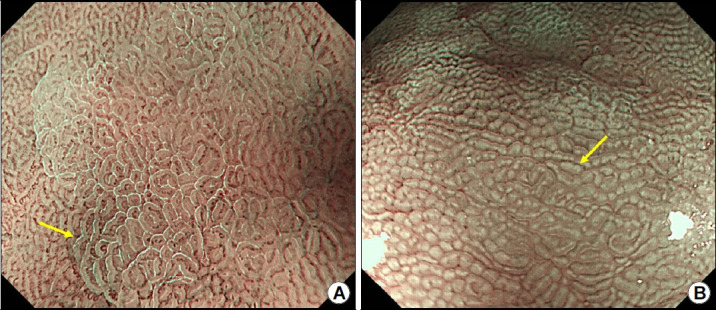

{"title":"[Clinical Application of the Kyoto Classification of Gastritis].","authors":"Gwang Ha Kim","doi":"10.7704/kjhugr.2023.0013","DOIUrl":null,"url":null,"abstract":"<p><p>Recent advances in endoscopic technology, including high-definition and image-enhanced endoscopy such as narrow-band imaging have facilitated close observation and detailed imaging of the gastric mucosa. Currently, endoscopy is performed in Korea primarily for evaluation of premalignant conditions and gastric cancer detection. Recent research has established the Kyoto classification of gastritis, a novel grading system for endoscopic gastritis, which enables prediction of <i>Helicobacter pylori (H. pylori)</i> infection. The Kyoto classification score is calculated based on the sum of scores for five main items (of 19 endoscopic findings indicative of <i>H. pylori</i> infection) such as atrophy, intestinal metaplasia, enlarged gastric folds, nodularity, and diffuse redness with/without regular arrangement of collecting venules (RAC). Of these five endoscopic findings, atrophy, intestinal metaplasia, enlarged gastric folds, and nodularity are associated with an increased risk and RAC with a decreased risk of gastric cancer. Previous studies have reported that a Kyoto classification score ≥2 indicates current or past <i>H. pylori</i> infection. An increase in the Kyoto classification score is associated with a high risk of gastric cancer; specifically, a Kyoto classification score ≥4 indicates a high risk of gastric cancer. However, <i>H. pylori</i> eradication is followed by disappearance of enlarged gastric folds, nodularity, and diffuse redness; therefore, this grading system cannot accurately reflect the gastric cancer risk in patients with previous <i>H. pylori</i> infection. Limited studies have discussed the Kyoto classification of gastritis in Korea. Therefore, further large-scale multicenter studies are warranted for validation of the Kyoto classification to predict <i>H. pylori</i> infection and gastric cancer risk.</p>","PeriodicalId":22895,"journal":{"name":"The Korean Journal of Helicobacter and Upper Gastrointestinal Research","volume":" ","pages":"89-98"},"PeriodicalIF":0.0000,"publicationDate":"2023-06-01","publicationTypes":"Journal Article","fieldsOfStudy":null,"isOpenAccess":false,"openAccessPdf":"https://www.ncbi.nlm.nih.gov/pmc/articles/PMC12021524/pdf/","citationCount":"0","resultStr":null,"platform":"Semanticscholar","paperid":null,"PeriodicalName":"The Korean Journal of Helicobacter and Upper Gastrointestinal Research","FirstCategoryId":"1085","ListUrlMain":"https://doi.org/10.7704/kjhugr.2023.0013","RegionNum":0,"RegionCategory":null,"ArticlePicture":[],"TitleCN":null,"AbstractTextCN":null,"PMCID":null,"EPubDate":"2023/6/2 0:00:00","PubModel":"Epub","JCR":"","JCRName":"","Score":null,"Total":0}

Recent advances in endoscopic technology, including high-definition and image-enhanced endoscopy such as narrow-band imaging have facilitated close observation and detailed imaging of the gastric mucosa. Currently, endoscopy is performed in Korea primarily for evaluation of premalignant conditions and gastric cancer detection. Recent research has established the Kyoto classification of gastritis, a novel grading system for endoscopic gastritis, which enables prediction of Helicobacter pylori (H. pylori) infection. The Kyoto classification score is calculated based on the sum of scores for five main items (of 19 endoscopic findings indicative of H. pylori infection) such as atrophy, intestinal metaplasia, enlarged gastric folds, nodularity, and diffuse redness with/without regular arrangement of collecting venules (RAC). Of these five endoscopic findings, atrophy, intestinal metaplasia, enlarged gastric folds, and nodularity are associated with an increased risk and RAC with a decreased risk of gastric cancer. Previous studies have reported that a Kyoto classification score ≥2 indicates current or past H. pylori infection. An increase in the Kyoto classification score is associated with a high risk of gastric cancer; specifically, a Kyoto classification score ≥4 indicates a high risk of gastric cancer. However, H. pylori eradication is followed by disappearance of enlarged gastric folds, nodularity, and diffuse redness; therefore, this grading system cannot accurately reflect the gastric cancer risk in patients with previous H. pylori infection. Limited studies have discussed the Kyoto classification of gastritis in Korea. Therefore, further large-scale multicenter studies are warranted for validation of the Kyoto classification to predict H. pylori infection and gastric cancer risk.